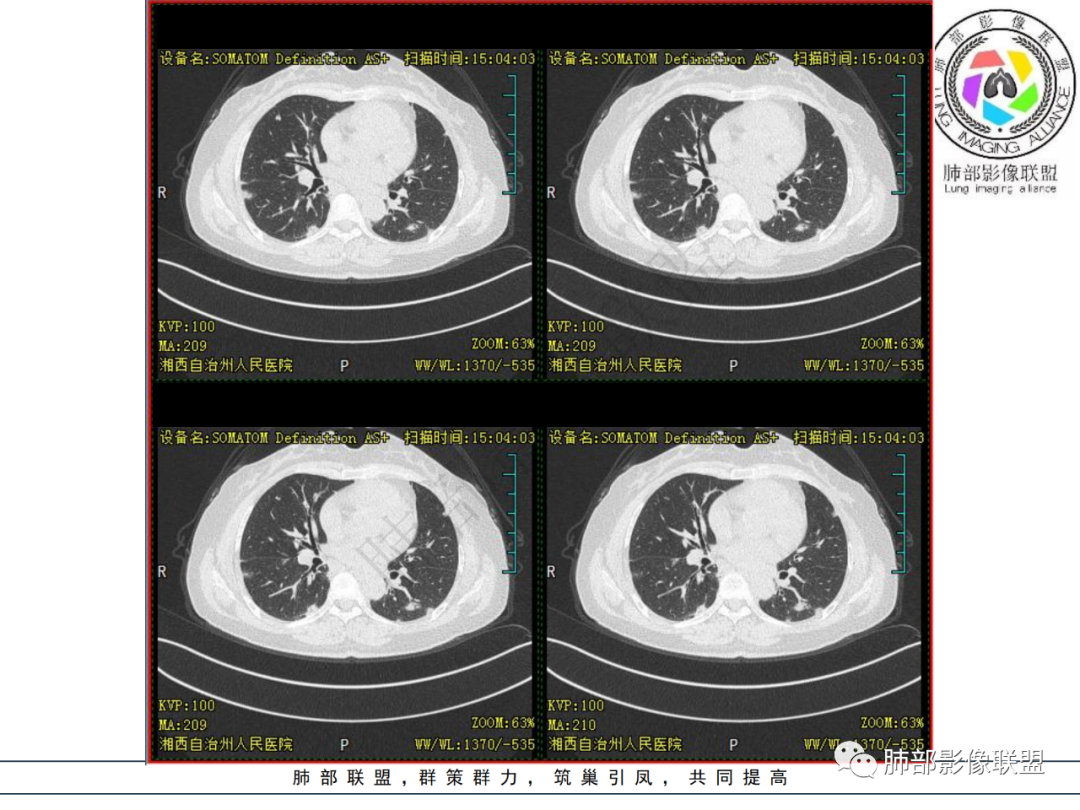

1.中年女性,发现双肺多发病变,且增多增大。

缺乏呼吸道症状及中毒症状,实验室炎性指标不高

既往多关节肿痛一年余,被诊断“类风湿”。此次就医无关节肿痛。

2.双肺多发片状影,胸膜下分布为主,部分沿支气管血管束分布,边界不清,实性及磨玻璃密度,趋于柔和,可见支气管进入或穿行,未见空洞、钙化及树芽等。部分病灶显示反晕。

3.未见腔积液。

4.双肺门及纵隔未见增大淋巴结。